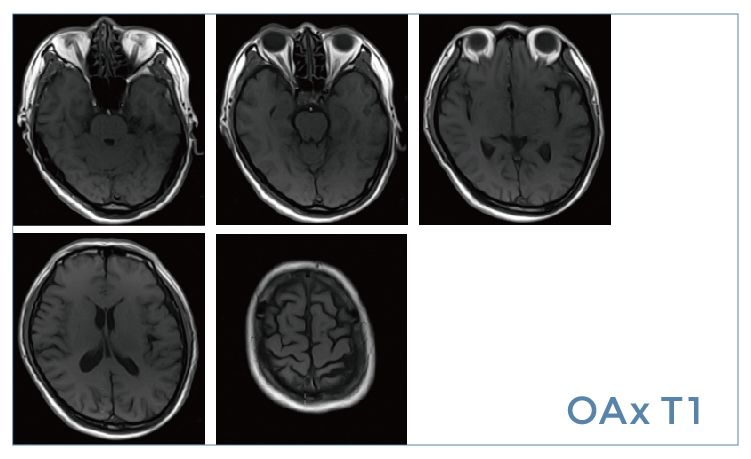

【朗润影像档案】20190524磁共振影像病例结果讨论